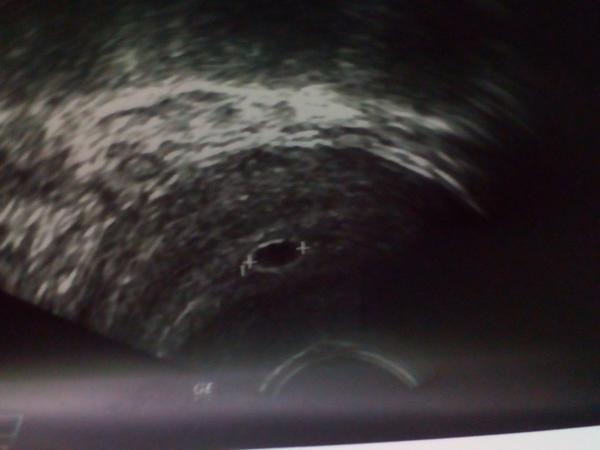

@peta73 moc děkuji a taky ti moc držím palce 🙂 no my měli jít na to IUI ted 8.9., ale když se nám mezitím zadařilo, tak už jsme to nepotřebovali. Možná, kdyby to nedopadlo takhle, tak jsme taky už byli objednání na další návštěvu a třeba by to dopadlo i lépe než teď ☹ Přece jen by hlídali ty vajíčka, jestli velikostí odpovídají jak mají. Já totiž nechodil a po tom clistilbegytu na žádné utz jako většina holek tady a možná to vajíčko bylo špatné velikosti, to co bylo oplodněno, proto řekl ten primář, že na utz ted bylo poznat, že od začátku něco bylo špatně. Že už to vajíčko nebylo jak mělo být.

@kaccka89 takto jsem to mela ja... A bohuzel to dopadlo zamlkle a revizi... Nechci te ale strasit!

Ale treba budes mit vetsi stesti nez ja!!! Mne doktor, co mi prováděl zakrok, rikal uz jen co by v jak velkém vacku melo byt, ze to nebral dle ms. Mohla si otěhotnět pozdeji, pokud mas delsi cykly...